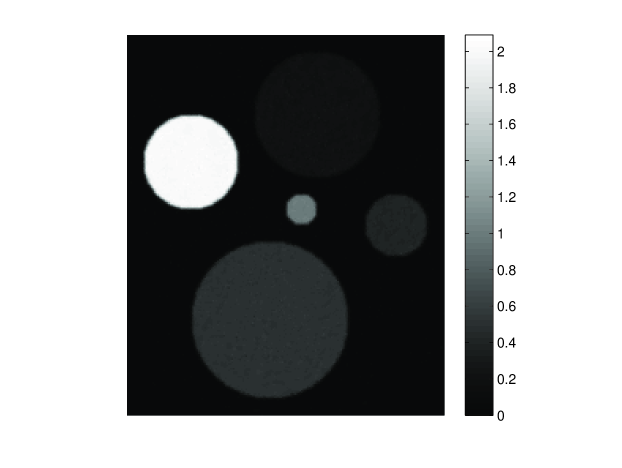

Investigation of systematic errors: The SOS and density maps employed in the simulation studies were representative of a monkey skull [10]. The dimensions of the skull were approximately 777 cm ×\times 666 cm, and its thickness ranges from 2 to 4 mm. Figure 2-(a) and (b) show a transverse slice of the SOS and density maps, which were used in the 2D simulations.

Figure 2: A slice of the SOS (a) and density (b) map deduced from the X-ray CT data of a monkey skull. Panel (c) and (d) display profiles of the SOS and density maps along the ‘X’-axis indicated in Fig. 2, respectively. Red dashed lines are the profiles of the assumed maps, whereas the blue solid lines are the profiles of maps with errors.

Since errors in the estimated SOS and density maps are inevitable regardless in how they are determined, we investigated the robustness of the reconstruction methods with respect to the SOS and density map errors, which were generated in two steps. First, 1.3% (with respect to maximum value) uncorrelated Gaussian noise with mean value of 1.7% of the maximum value was added to the SOS and density maps to simulate inaccuracy of the SOS and density values. Subsequently, the maps were shifted by 7 pixels (1.4 mm) to simulate a registration error. Figure 2-(c) and (d) show profiles of the SOS and density maps with those errors along the ‘X’-axis indicated by the arrows in Fig. 2-(a) and (b), respectively.